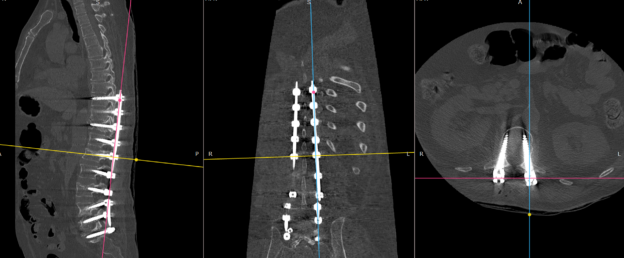

- Surgical Treatment:

- In severe fractures, surgery might be needed to stabilize the bones and restore function.

- Vertebroplasty and Kyphoplasty: These minimally invasive surgeries involve injecting bone cement into fractured vertebrae to stabilize them and relieve pain.